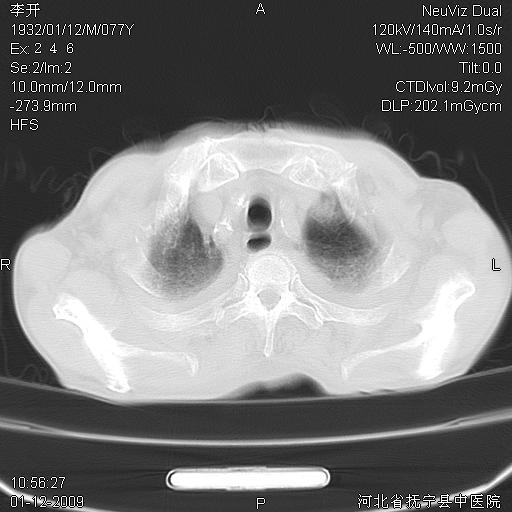

以下是引用黑白光影在2009-1-19 16:49:00的发言:[br]心衰肺水肿;心包、胸腔积液;冠脉钙化;肺部感染。